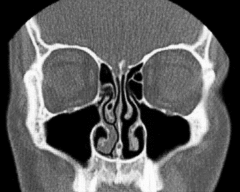

In der Medizin wird eine Frontalebene des Kopfes auch als Coronalebene oder Koronalebene bezeichnet. Insbesondere bei der tomographischen Bildgebung spielen Frontalschnitte – meist Koronalschnitte oder Koronarschnitte genannt – als parallel zu einer Frontalebene aufgenommene oder nachträglich in dieser Orientierung rekonstruierte Bilddaten eine wichtige Rolle. Aus der tomographischen Untersuchung in dieser Ebene ergeben sich die koronalen Schichtungen, die den Körper eines untersuchten Patienten so darstellen, dass sich von vorne nach hinten aufeinanderfolgende Schichten betrachten lassen.[1]